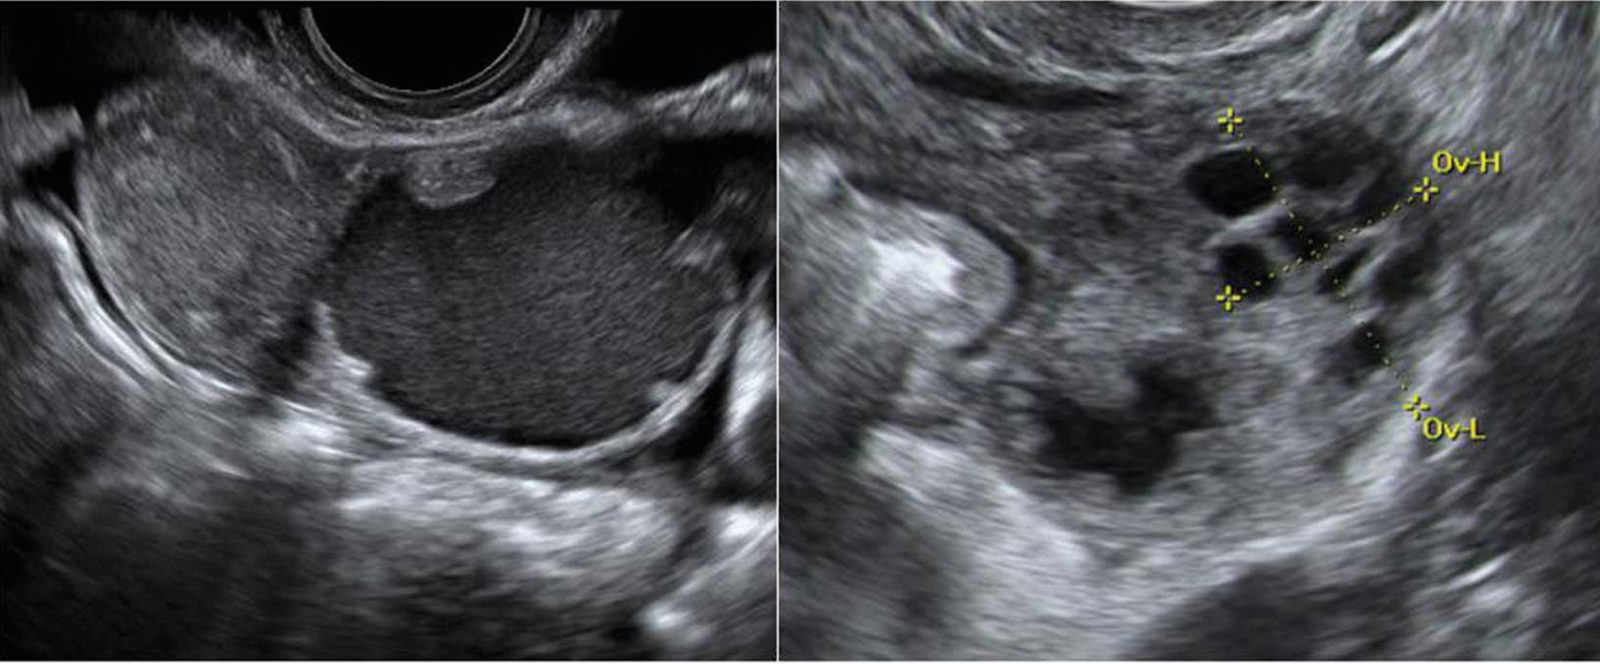

Un absceso tubo-ovárico (AOT) es una infección pélvica grave que puede afectar tanto a las trompas de Falopio como a los ovarios. Esta condición, que generalmente se origina por la propagación de bacterias desde la vagina o el cuello uterino, es comúnmente asociada con la enfermedad inflamatoria pélvica (EIP). Si no se trata a tiempo, puede generar complicaciones severas. Los síntomas incluyen dolor abdominal intenso, fiebre, alteraciones en el ciclo menstrual y flujo vaginal anormal.